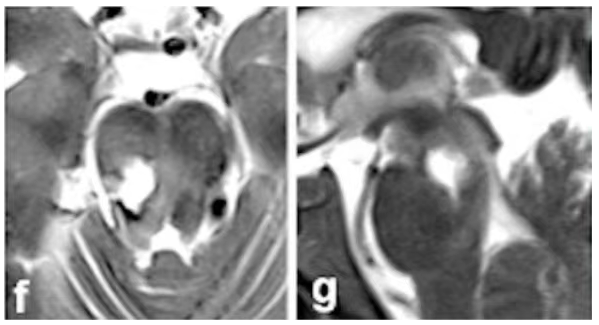

术后影像(图f-g)

手术的成功只是第一步,更令人欣喜的是患者的康复速度!术后,他一度丧失的神经功能开始了快速而显著的恢复。

在术后6个月的关键随访节点上,检查结果让所有人振奋:患者没有遗留任何永久性的神经功能缺损!